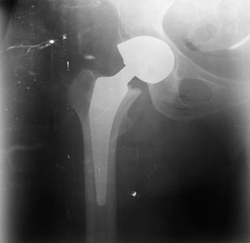

64-year-old woman with a history of type 2 diabetes mellitus was admitted for

total hip arthroplasty (THA) following a left femoral neck fracture (Figure1). The patient had no known

Figure 1: Total hip arthroplasty (THA)